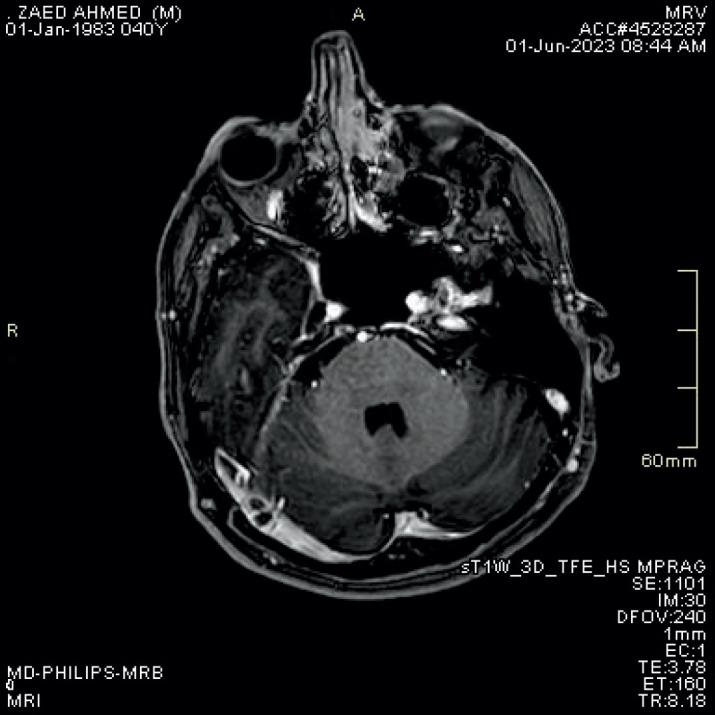

Post -contrast Three -dimensional MP RAGE T1WI Sequence Compared to Brain MRV Sequence for Diagnosing Brain Sinus Venous Thrombosis.

Background: Dural sinus thrombosis is considered as a one of the clinical and radiological emergencies that require special attention and high index of suspicion and needs combined effort of both the treating physician and the radiologist to obtain proper diagnosis and subsequently proper management.

Objective: The aim of this article was to compare the accuracy of MRV TOF and post contrast MP-RAGE sequences in diagnosis of cerebral sinus venous thrombosis.

Methods: After all informed consents were obtained and upon ethical committee approval from the ethical committee in Joradanian Royal medical services in Amman we perform this study as a retrospective study done on 50 patients with cerebral sinus venous thrombosis with 50 pateints control group done at king Hussein medical center in Amman Jordan.

Results: The guidelines and regulations of studies conducted in Royal medical services were followed. 68 females and 32 males with age range between 19 and 52 years. All patients underwent brain MRI for evaluation of cerebral sinus thrombosis, all studies were done on seimens skyra 3 Tesla machine with standardized protocol including 2 D TOF MRV, axial T2WI, axial FLAIR, Axial T1, SWI and diffusion weighted images along with 3D MP-RAGE post contrast. Images were reviewed by two well experienced neuroradiologists (Maysoon and Qamar) in separate sessions, each MRI sequence was reported separately without knowing patients name or clinical history. Conclusion: The results for T2 WI, SWI, MRV TOF and MP-RAGE post contrast were reported. We used a confidence level score to standardize the results. Then the results were analyzed using simple statistical methods.